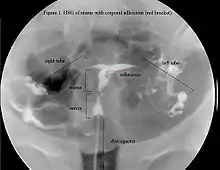

La historia del acontecimiento del embarazo seguido por la dilatación y el legrado liderizado por la amenorrea secundaria o a la hipomenorrea es común. La histeroscopia es el estándar de oro para el diagnóstico. 3 La proyección de sonohisterografía o histerosalpingografía podría revelar el grado de la formación de la cicatriz. El ultrasonido no es un método confiable de diagnosticar el Síndrome de Asherman. Los estudios de la hormona muestran los niveles normales constantes con la función reproductiva.